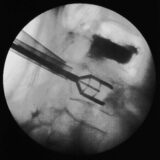

PRP is given to patients through an injection, and ultrasound guidance can assist in the precise placement of PRP. After the injection, a patient must avoid exercise for a short period of time before beginning a rehabilitation exercise program.